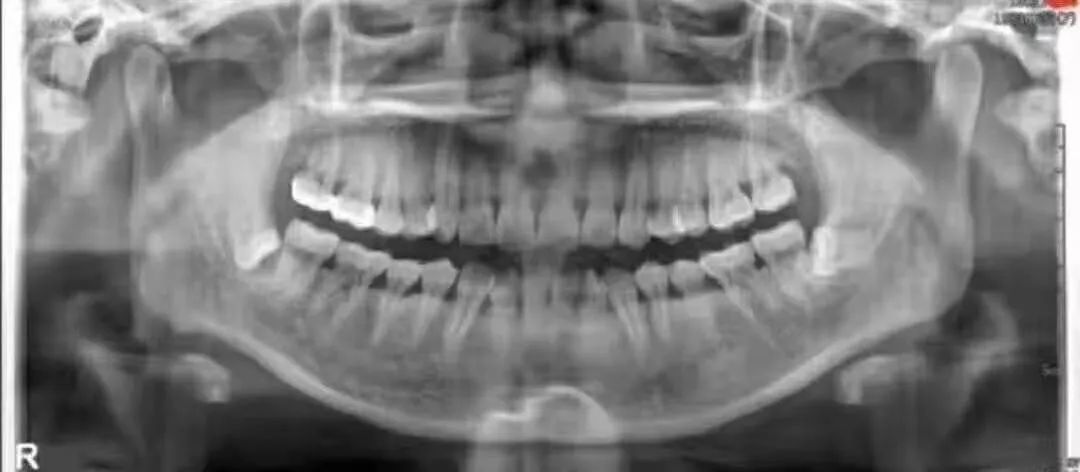

传说中收费14000的牙长这样子——

1.2 恰当检查 包括高质量的X线片,它不仅能提供牙齿的清晰图像,牙根的轮廓和解剖以及牙周骨质情况,还能提供牙齿与邻牙和其他结构之间的关系,其中尤其是下颌骨下缘、下颌骨升支以及下牙槽神经束之间的关系。